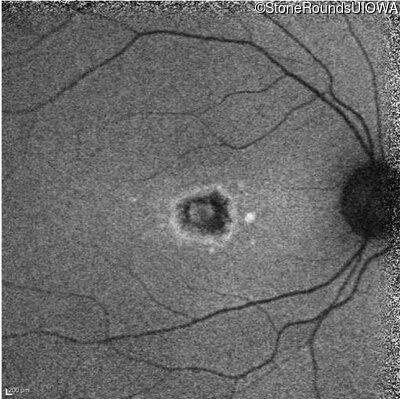

Infrared Fundus Photograph - Right - 20/25 -1

Exemplar